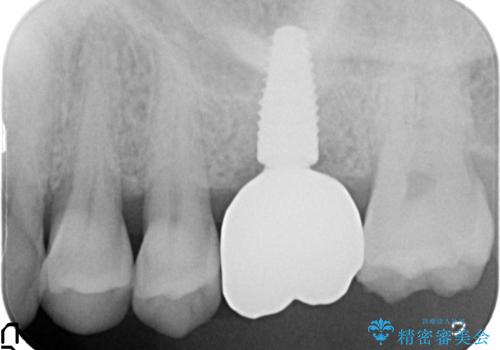

奥歯でしっかり噛める、インプラント治療

- 奥歯に入れていたブリッジがダメになり歯を抜去、全然噛めなくなった、インプラント治療を受けたい!と奥歯の機能回復を希望され来院されました。

奥歯はすでに3本失った状態で、この状態で歯を入れるには「入れ歯」か、「インプラント」の2択となります。

入れ歯ではなくしっかりと噛んで食事を楽しみたい。という強い希望から、インプラント治療を進めていくこととなりました。

- 110万円(インプラント×2・チタンカスタムアバットメント×2・ジルコニアクラウン×3・仮歯×3)費用は治療当時の料金となります

しっかりと噛めるようになったことで、また食事を楽しんでいただくことができるようになりました。